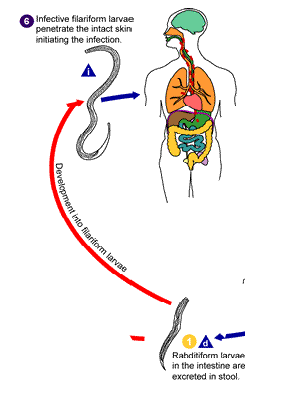

steps of s stercoralis life cycle

infective filariform larvae penetrate skin

filariform enter circulation or lungs where they are swallowed & enter small intestine

rhabditiform excreted in stool

rhabditiform → filariform → penetrate skin

Rhabditiform larvae hatch from egg, mature into filariform larvae

Penetrate intact skin of human host

Moves into the auto-infective cycle from there